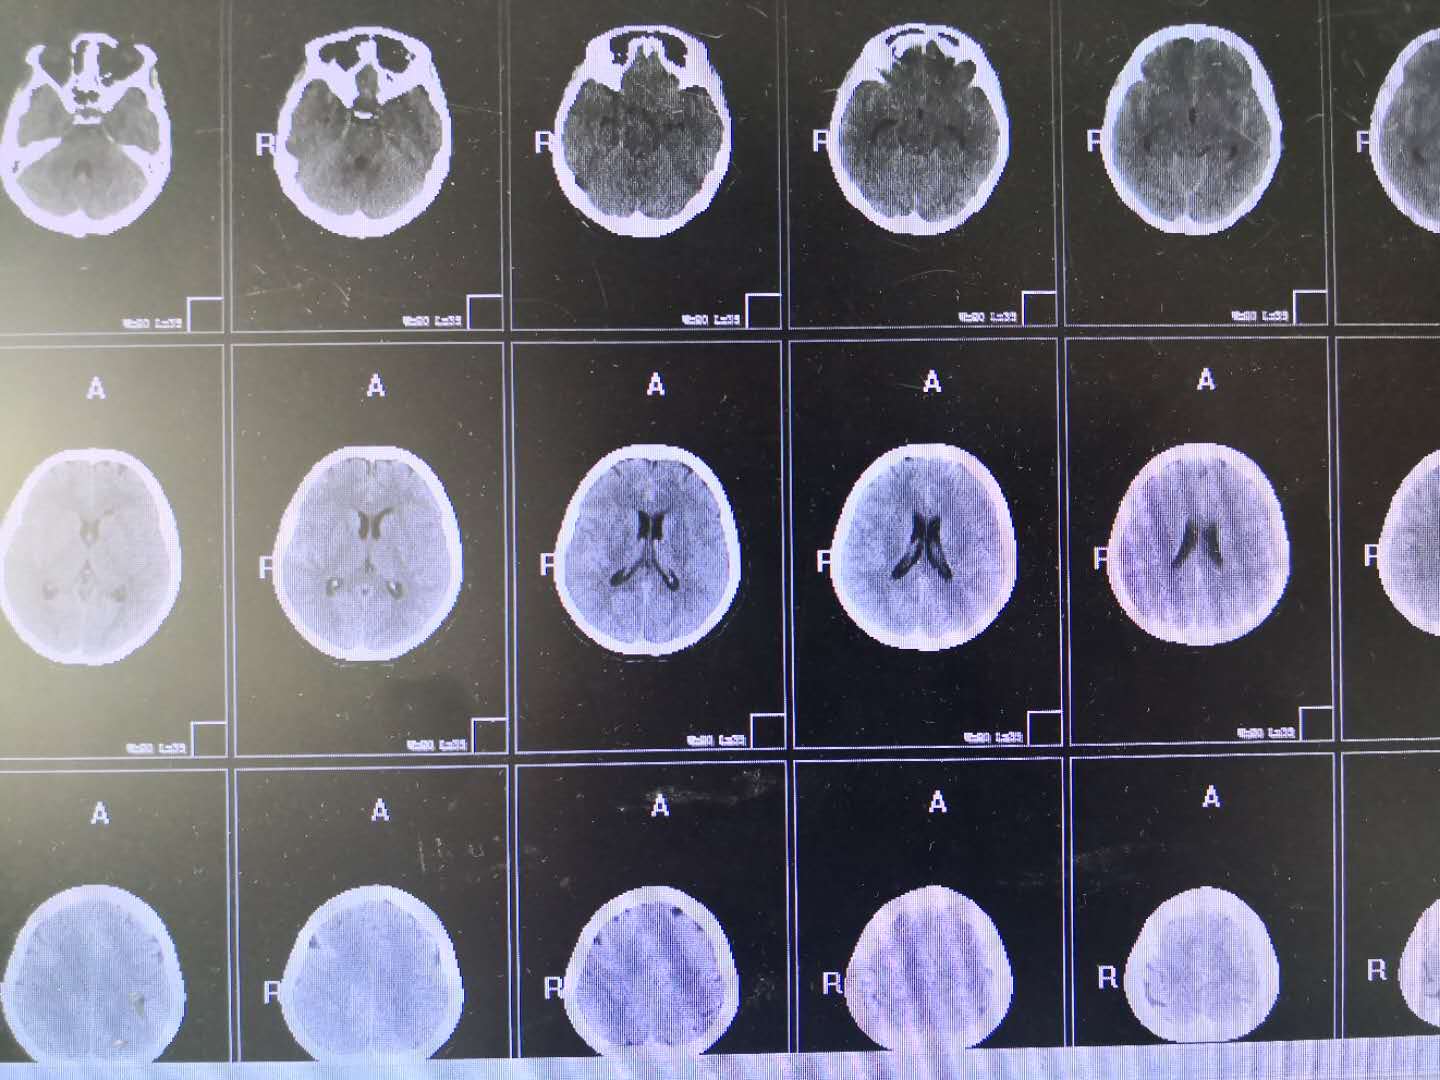

2018年8月6日凌晨,一名剧烈头痛患者被120急救车送入我院,行脑CT检査后以“蛛网膜下腔出血”收入神经内二科,患者病情危重,出血如果再次增多直接压迫生命中枢随时可能出现生命危险,值班医师临危不惧,凭借多年的经验积极对症治疗。2天后患者病情较前平稳,行颅脑MRA提示:颈内动脉动脉瘤,结合患者病情,如不处理,随时有可能出血,危及生命,宜尽快手术。主管医生积极完善术前准备,由高磊主任于8月9日为患者行全脑血管造影术及支架辅助下动脉瘤微弹簧圈栓堵,术后患者恢复良好,不日治愈出院。